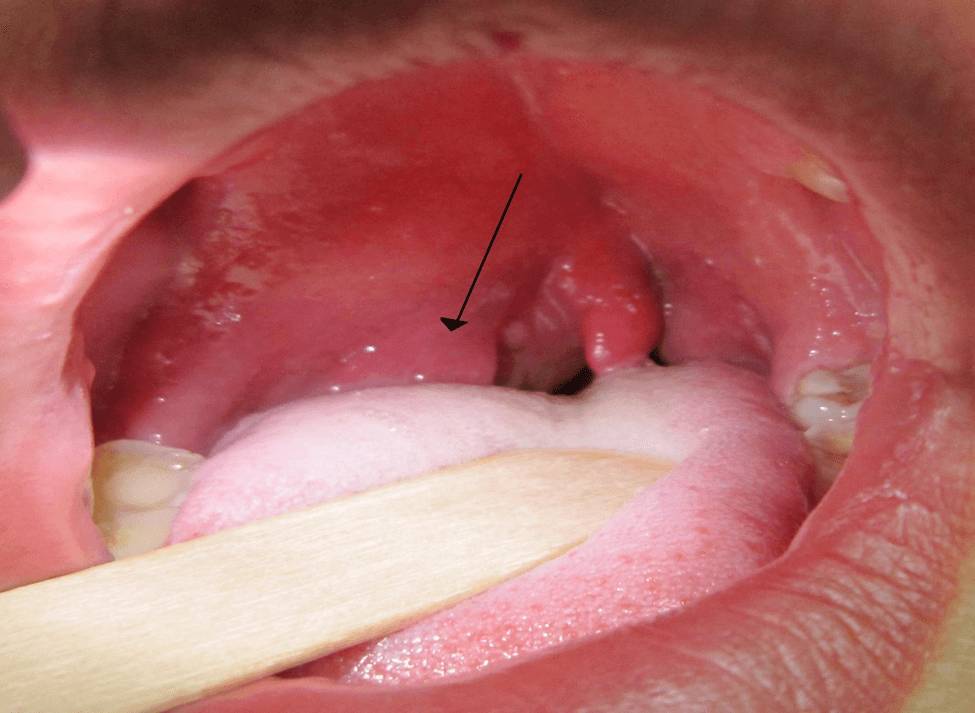

Проблемы с носом и гортанью

Наиболее характерные проявления для сезонных типов аллергии: на пыльцу цветов, запахи, тополиный пух. Носоглотка – это место первичного контакта с аллергенов, поэтому и симптоматика наиболее выражена именно в ее области. Проявляется аллергический ринит следующими симптомами:

- обильными, вытекающими выделениями из носа;

- чиханием;

- сухим кашлем;

- храпом (даже при бодрствовании);

- снижением обоняния.

Для коррекции состояния используются противоаллергические медикаменты, капли, морская вода для промывания слизистой, сосудосуживающие средства и иные методы симптоматической терапии.

Часто состояние развивается стремительно и перерастает в аллергический отек лица и гортани. Эти проявления особенно опасны для детей, так как в возрасте от 2 до 6 лет строение гортани ребенка отличается от взрослого узким отверстием.